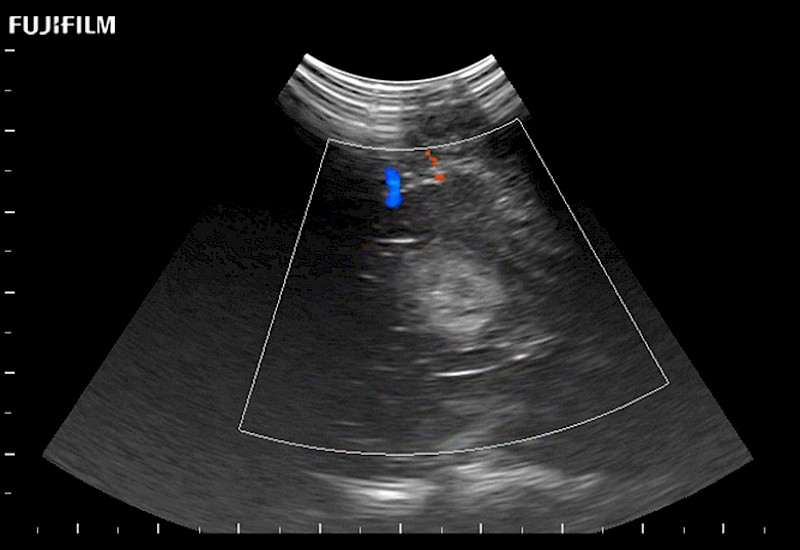

Exclusive 10mm side‐fire linear array transducer with 2.87mm diameter is ideal for real‐time visualization through and behind structures and instant, scalable definition of anatomy and vascularity including the ability to delineate and define tumor margins.

Main Specifications: